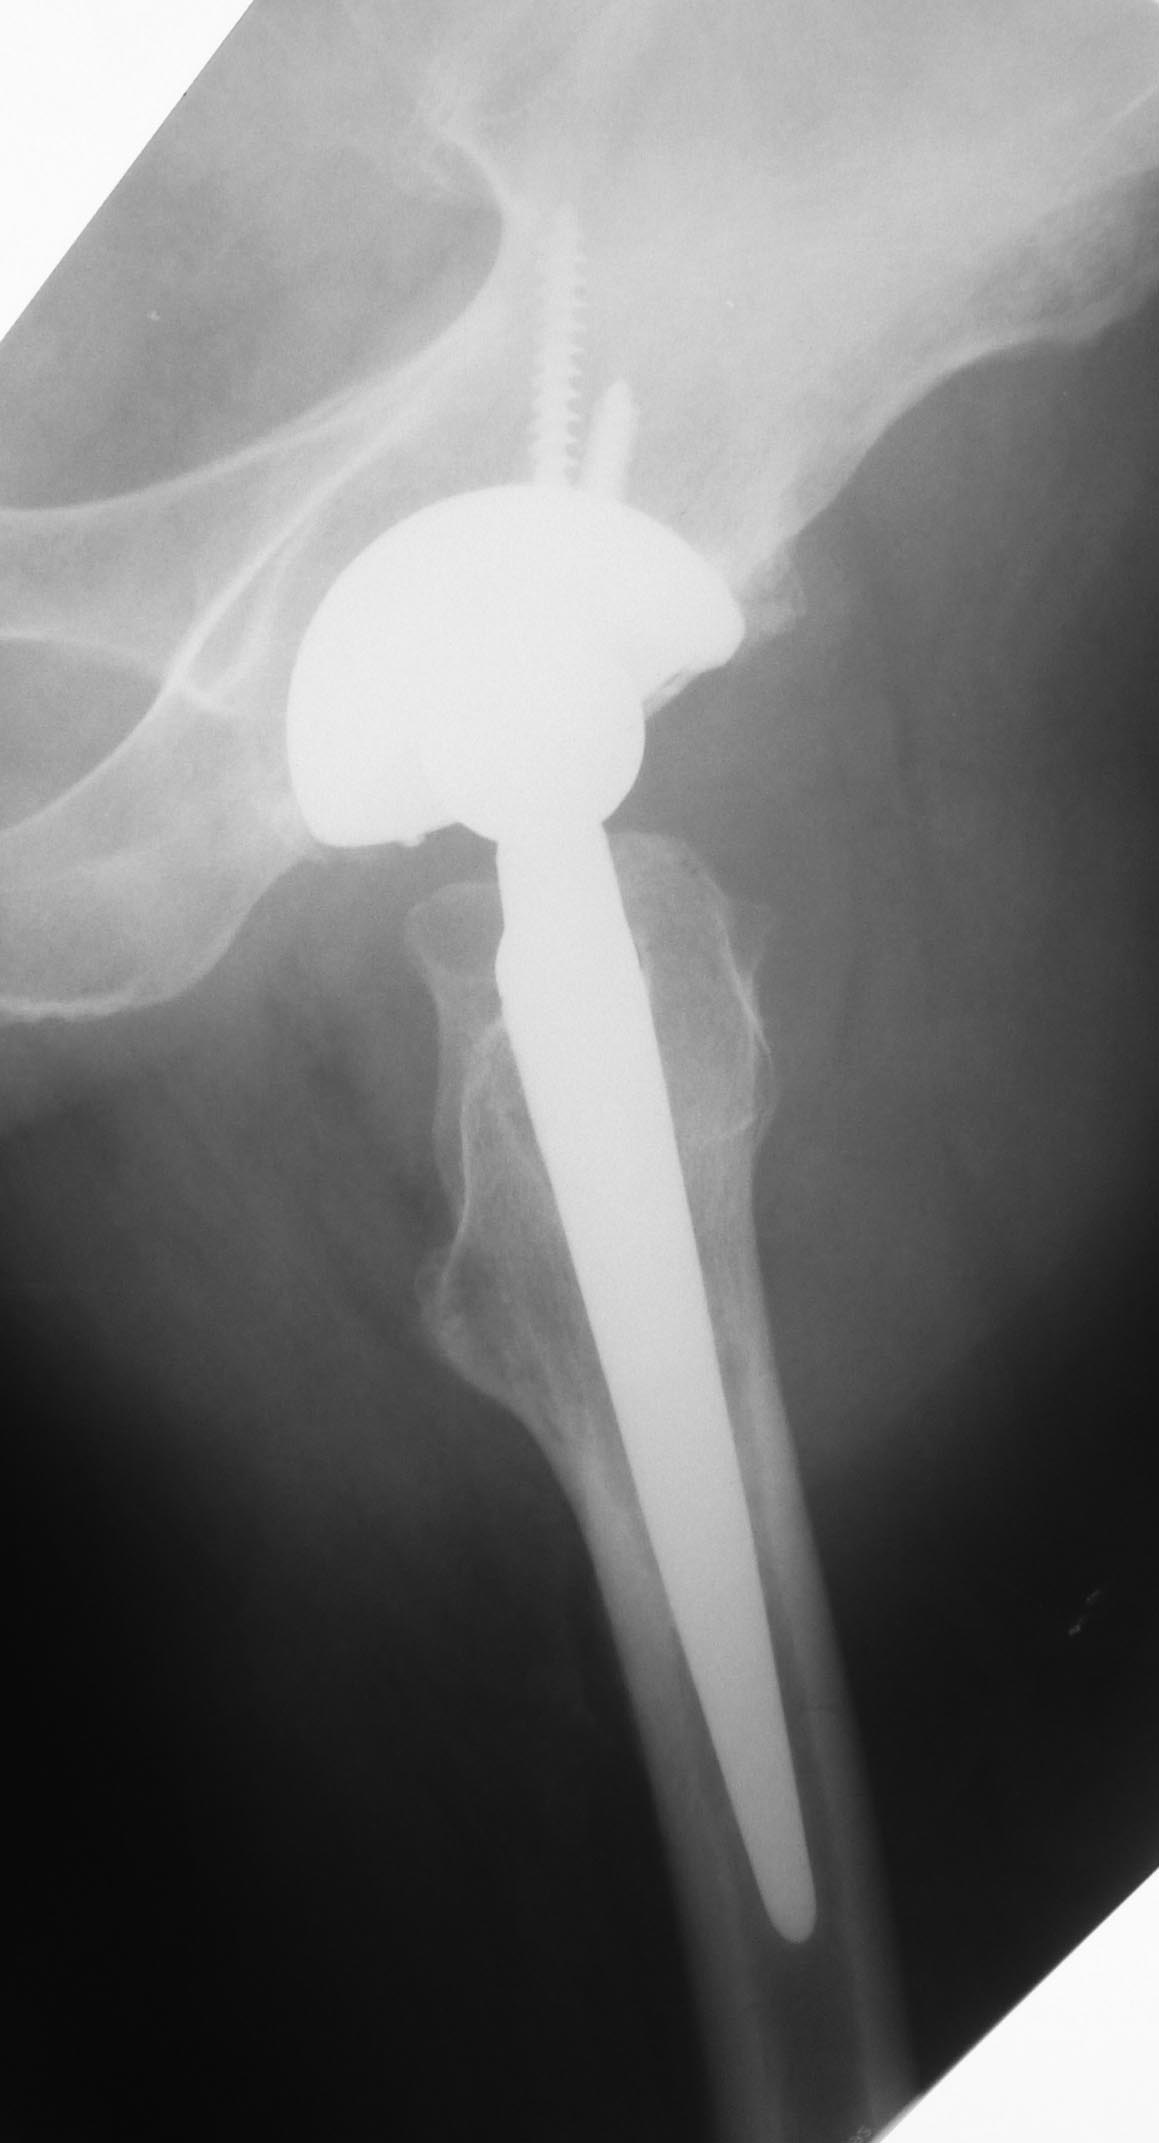

Уважаемые коллеги.Есть ли у кого-нибудь опыт сохранения эндопротеза при

связанном с травмой нагноением без признаков нестабильности протеза и

деструкции костной ткани?

Пациент 55 лет. 6 лет после эндопротезирования по поводу коксартроза. На

майские праздники упал со скамейки на ягодицу. За помощью обратился

только через месяц из-за слегка болезненной припухлости в области

ягодицы на стороне эндопротеза. При пункции под УЗ-контролем удалено

около 200 мл гноеподобной жидкости из области эндопротеза (пункция

выполнена через переднелатеральный доступ). Посев стерильный. Ни разу не

отмечена лихорадка. СОЭ 87, С-рб 67. Жидкость снова набралась за неделю.